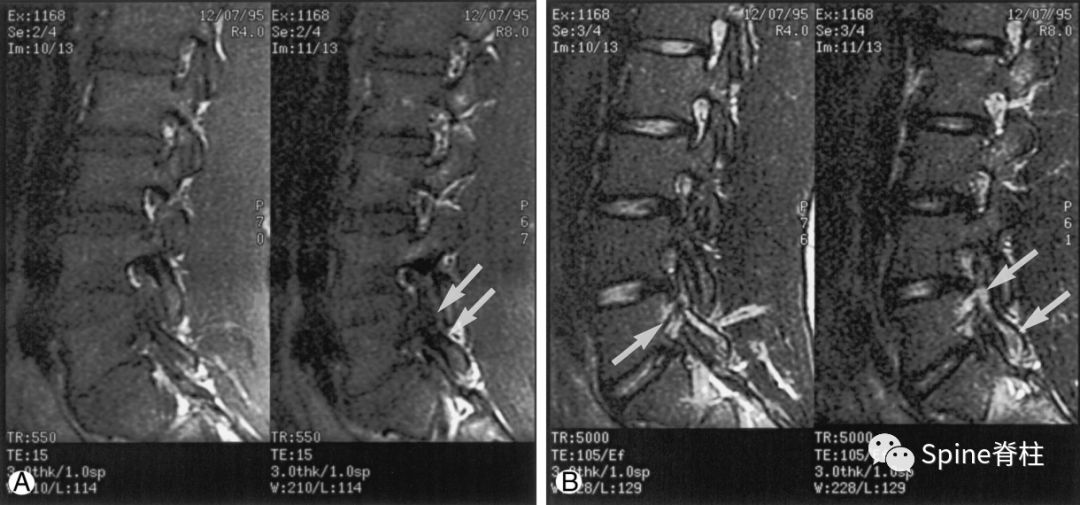

图:峡部完全断裂,断端存在明显间隙,且T2像明显水肿信号,提示L5左侧峡部裂(3级)

16岁的足球运动员,诉腰痛,以左侧为重。A:T1像可见腰5左侧峡部完全断裂(箭头);B:T2像,腰5左侧峡部、椎弓根和关节突水肿信号(箭头)

图:峡部完全断裂,但无T2水肿信号

提示为左侧L5峡部裂(4级)

13岁运动员,左侧腰骶部疼痛。A:T1像,左侧腰5峡部完全断裂(箭头);B:T2像,左侧腰5峡部清晰可见,骨质无信号改变,峡部缺损处可见轻微的高信号,提示可能为肉芽组织或积液